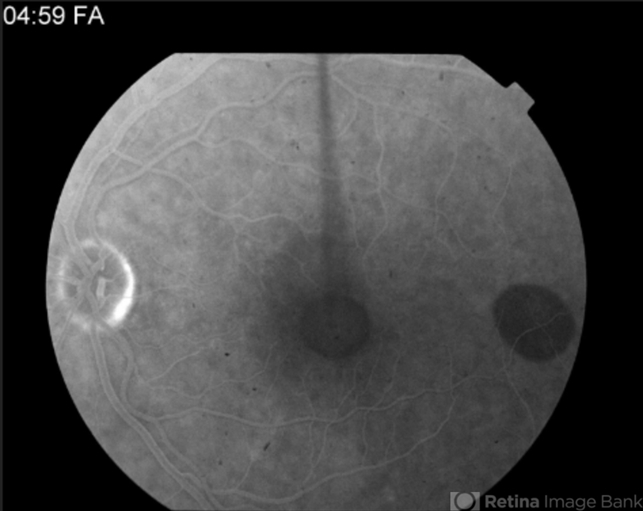

Multifocal Best Disease

Best disease, adult vitelliform dystrophy

Angiography reveals blocking defects due to pigment clumping with no evidence of CNVM.